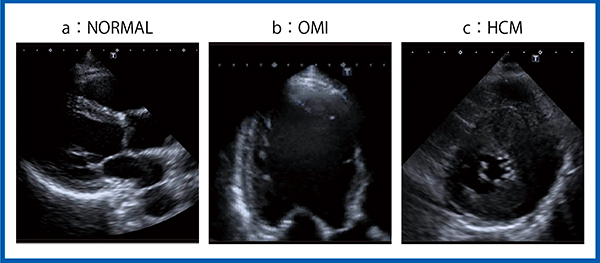

図9は,正常例,陳旧性心筋梗塞(OMI),肥大型心筋症(HCM)の画像であるが,心尖部の描出能が向上しており,陳旧性心筋梗塞の画像でも心尖部の輪郭を明瞭にとらえられている(図9 b)。肥大型心筋症の画像では,心筋性状の観察も可能である(図9 c)。

図9 Aplio iシリーズによる正常例(a),陳旧性心筋梗塞(b),肥大型心筋症(c)の画像